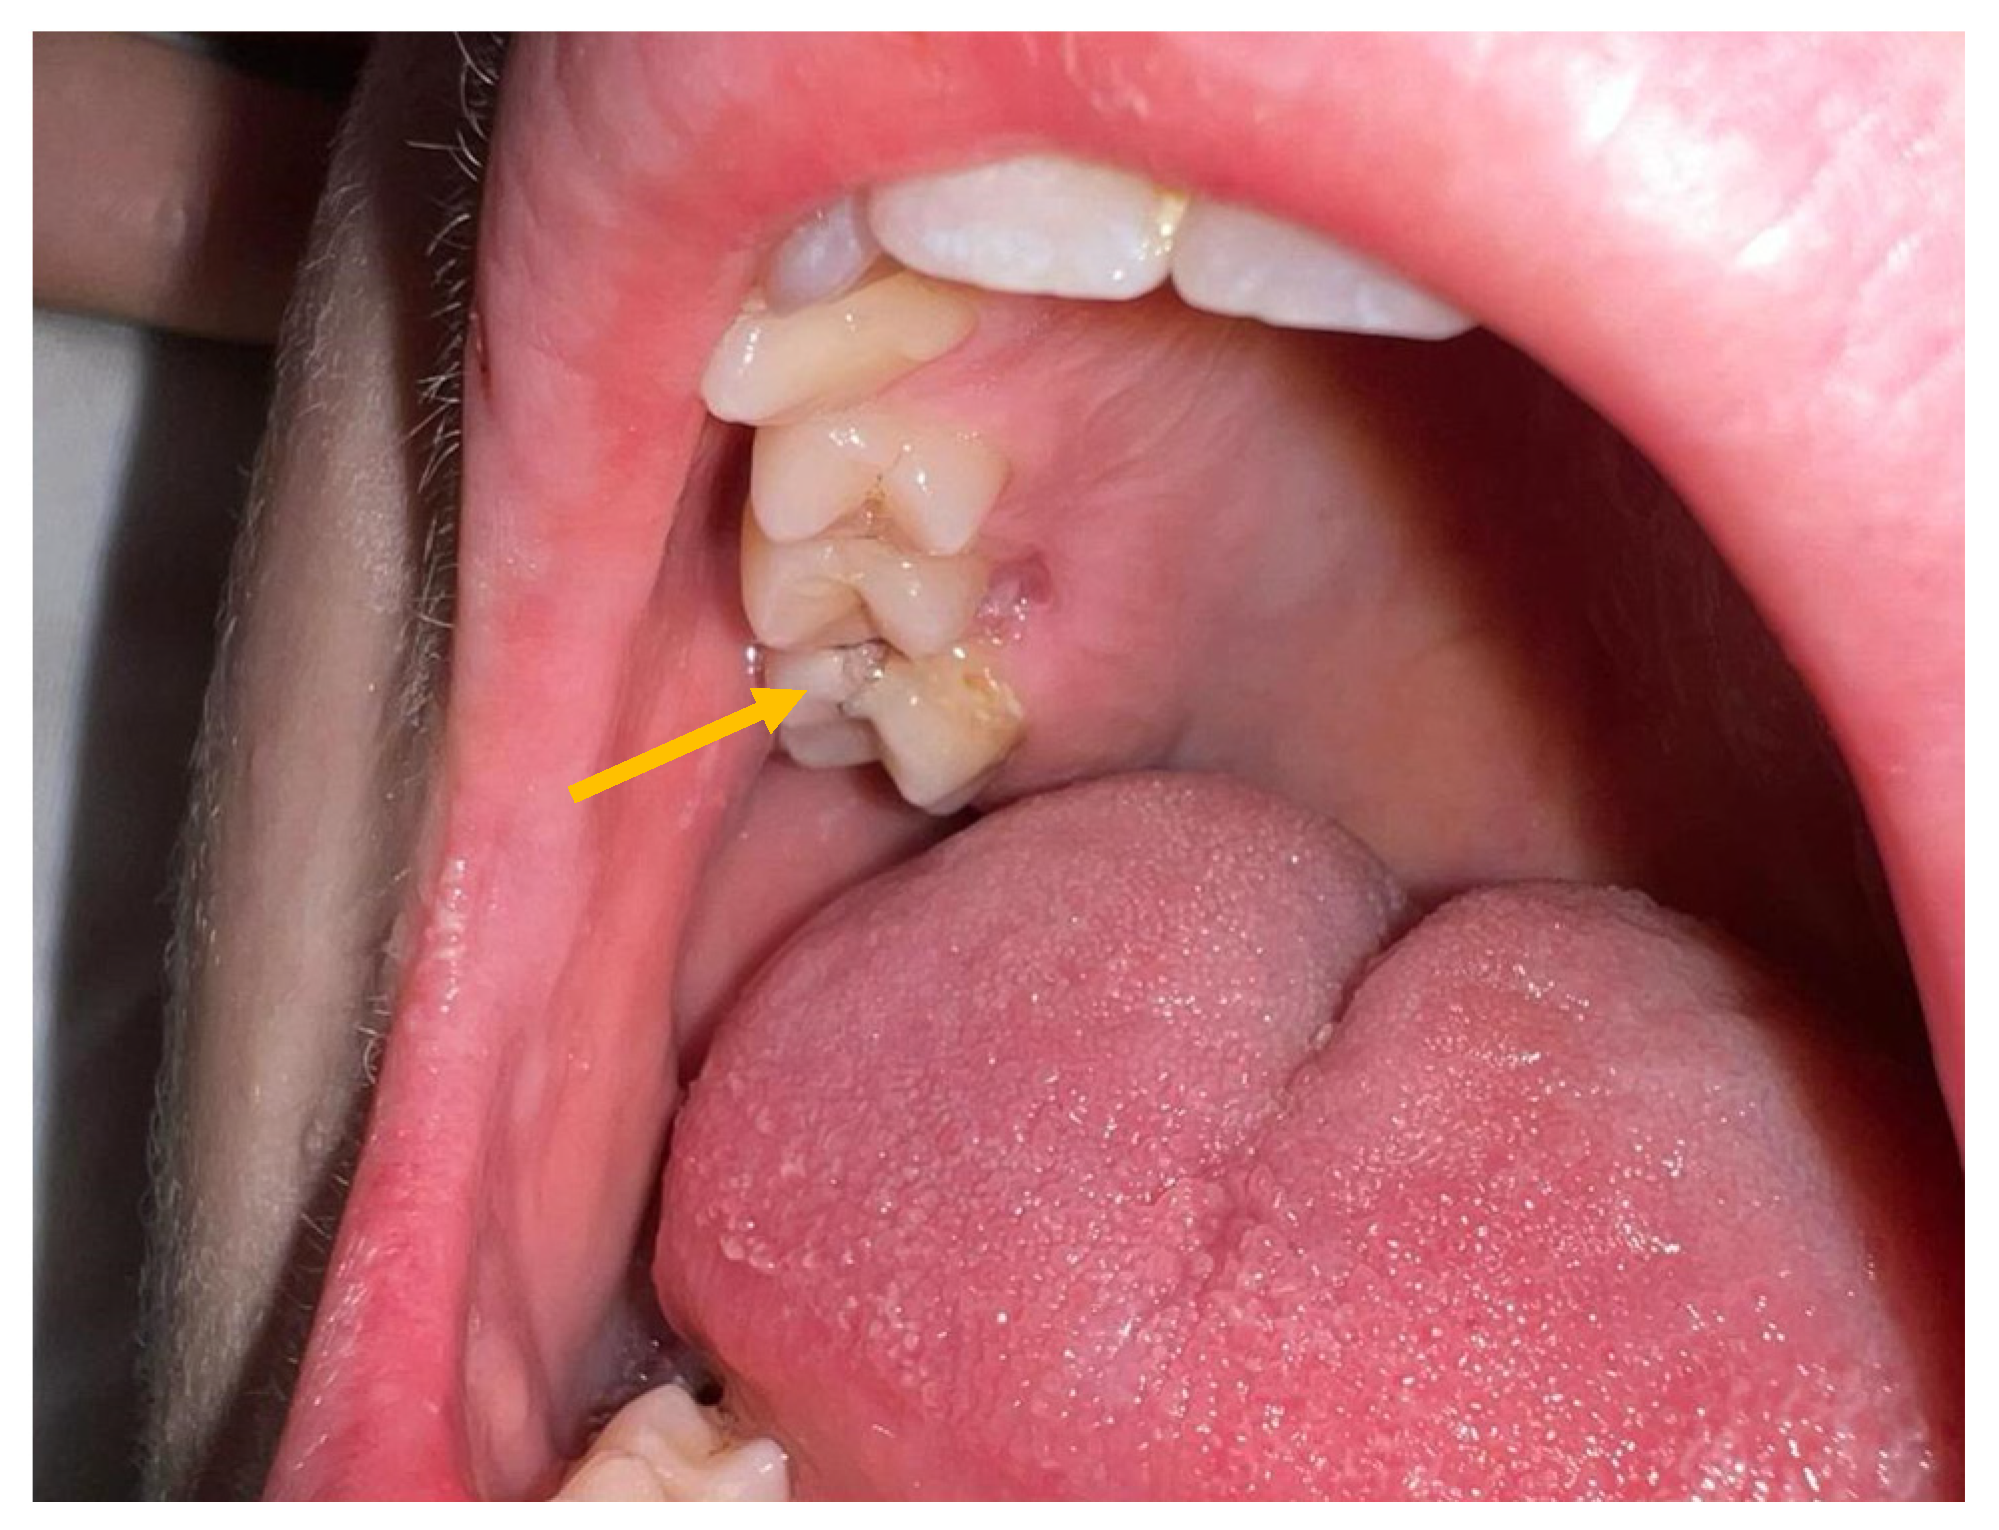

2. Case Report

| Colomba C. et al./Italy/2023 | 12 y | M | No | No | sinus drainage material | sinusitis, meningitis, CSVT | ceftriaxone + vancomycin + metronidazole → cefotaxime | healed |